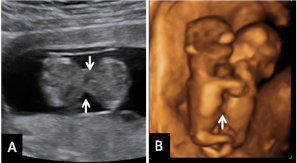

Ecografía Embarazo 2D y 3D Semana 12 - PRUEBAS DIAGNÓSTICAS